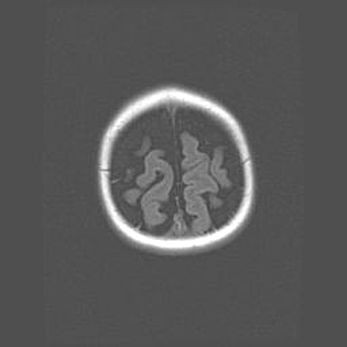

Наружная гидроцефалия с возможной атрофией височных областей.

Возраст: 28 дней

Вес: 3670 г

Пол: мужской

Окружность головы: 38 см

Срок гестации: 40 недель

Гидроцефалия головного мозга у новорожденных – это заболевание, которое характеризуется скоплением избыточного количества спинномозговой жидкости в желудочковой системе головного мозга в результате затруднения её перемещения от места выработки к месту поглощения в кровеносную систему или вследствие нарушения абсорбции. При открытой наружной форме гидроцефалии у новорожденных расширяются и переполняются субарахноидные пространства.

При нормотензивных  формах,  которые,  как  правило,  являются  следствием  перенесенных ишемических  повреждений  паренхимы  мозга,  возможно  сочетание микроцефалии  с нормотензивной гидроцефалией. В основе данных изменений лежит атрофия больших полушарий с преимущественной  локализацией  в  лобно-височных  областях.